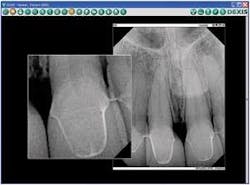

Seating displacement and incomplete seating of the restorations will lead to misalignment, open margins, and/or tight contacts. To minimize or eliminate seating issues, use a cementation index to carry all of the restorations to the mouth at once in the same alignment as on the model. Once the restorations are stabilized in the mouth, take radiographs for confirmation. The ease, speed, and magnification of digital X-rays are perfect for this task.